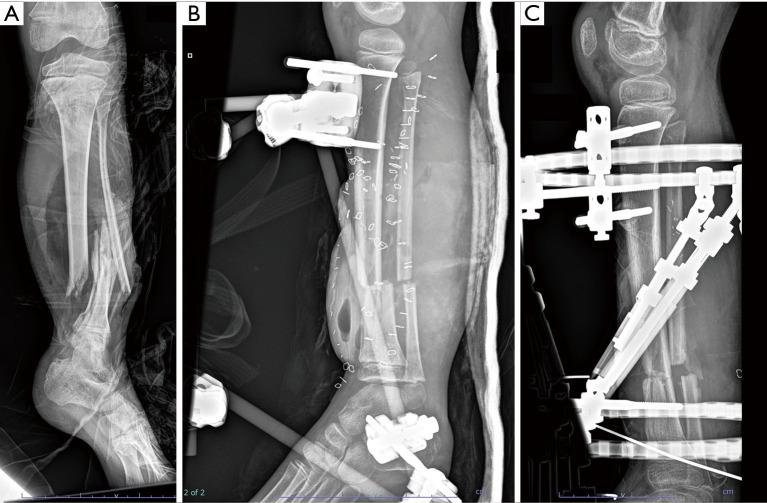

CASE DESCRIPTION

We present the case of a 16-year-old male with extensive left lower extremity osteomyelitis secondary to eight years after an open fracture to this leg was complicated by an infection with the same organism. Suboptimal therapy of his initial infection may have contributed to persistent, latent disease before recurrence years later. Evaluation for immunodeficiency was negative and he responded well to ciprofloxacin antibiotic therapy.

病例描述

我们报告一例16岁男性,其左下肢广泛骨髓炎继发于该腿部开放性骨折8年后,此次骨折因感染同一病原体而复杂化。他最初感染的治疗不充分可能导致了疾病持续存在、潜伏,直至数年之后复发。免疫缺陷评估为阴性,他对环丙沙星抗生素治疗反应良好。